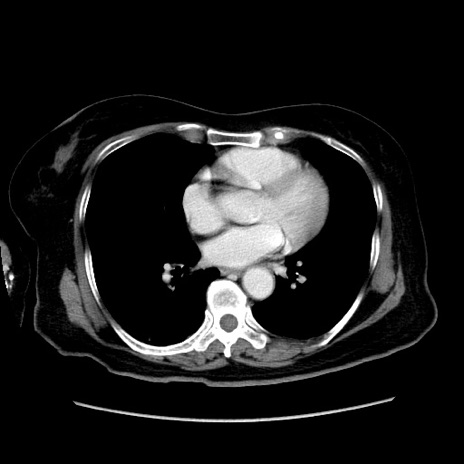

症例19(横断像)

【症例】80歳代女性

【主訴】下腹部痛

【現病歴】約8時間前より下腹部痛の出現あり、救急外来受診。

【既往歴】両側付属器切除

【身体所見】意識清明、下腹部正中に手術痕あり、その部位に一致して圧痛と反跳痛あり。腸蠕動音は亢進。

【データ】WBC 9300、CRP 0.15